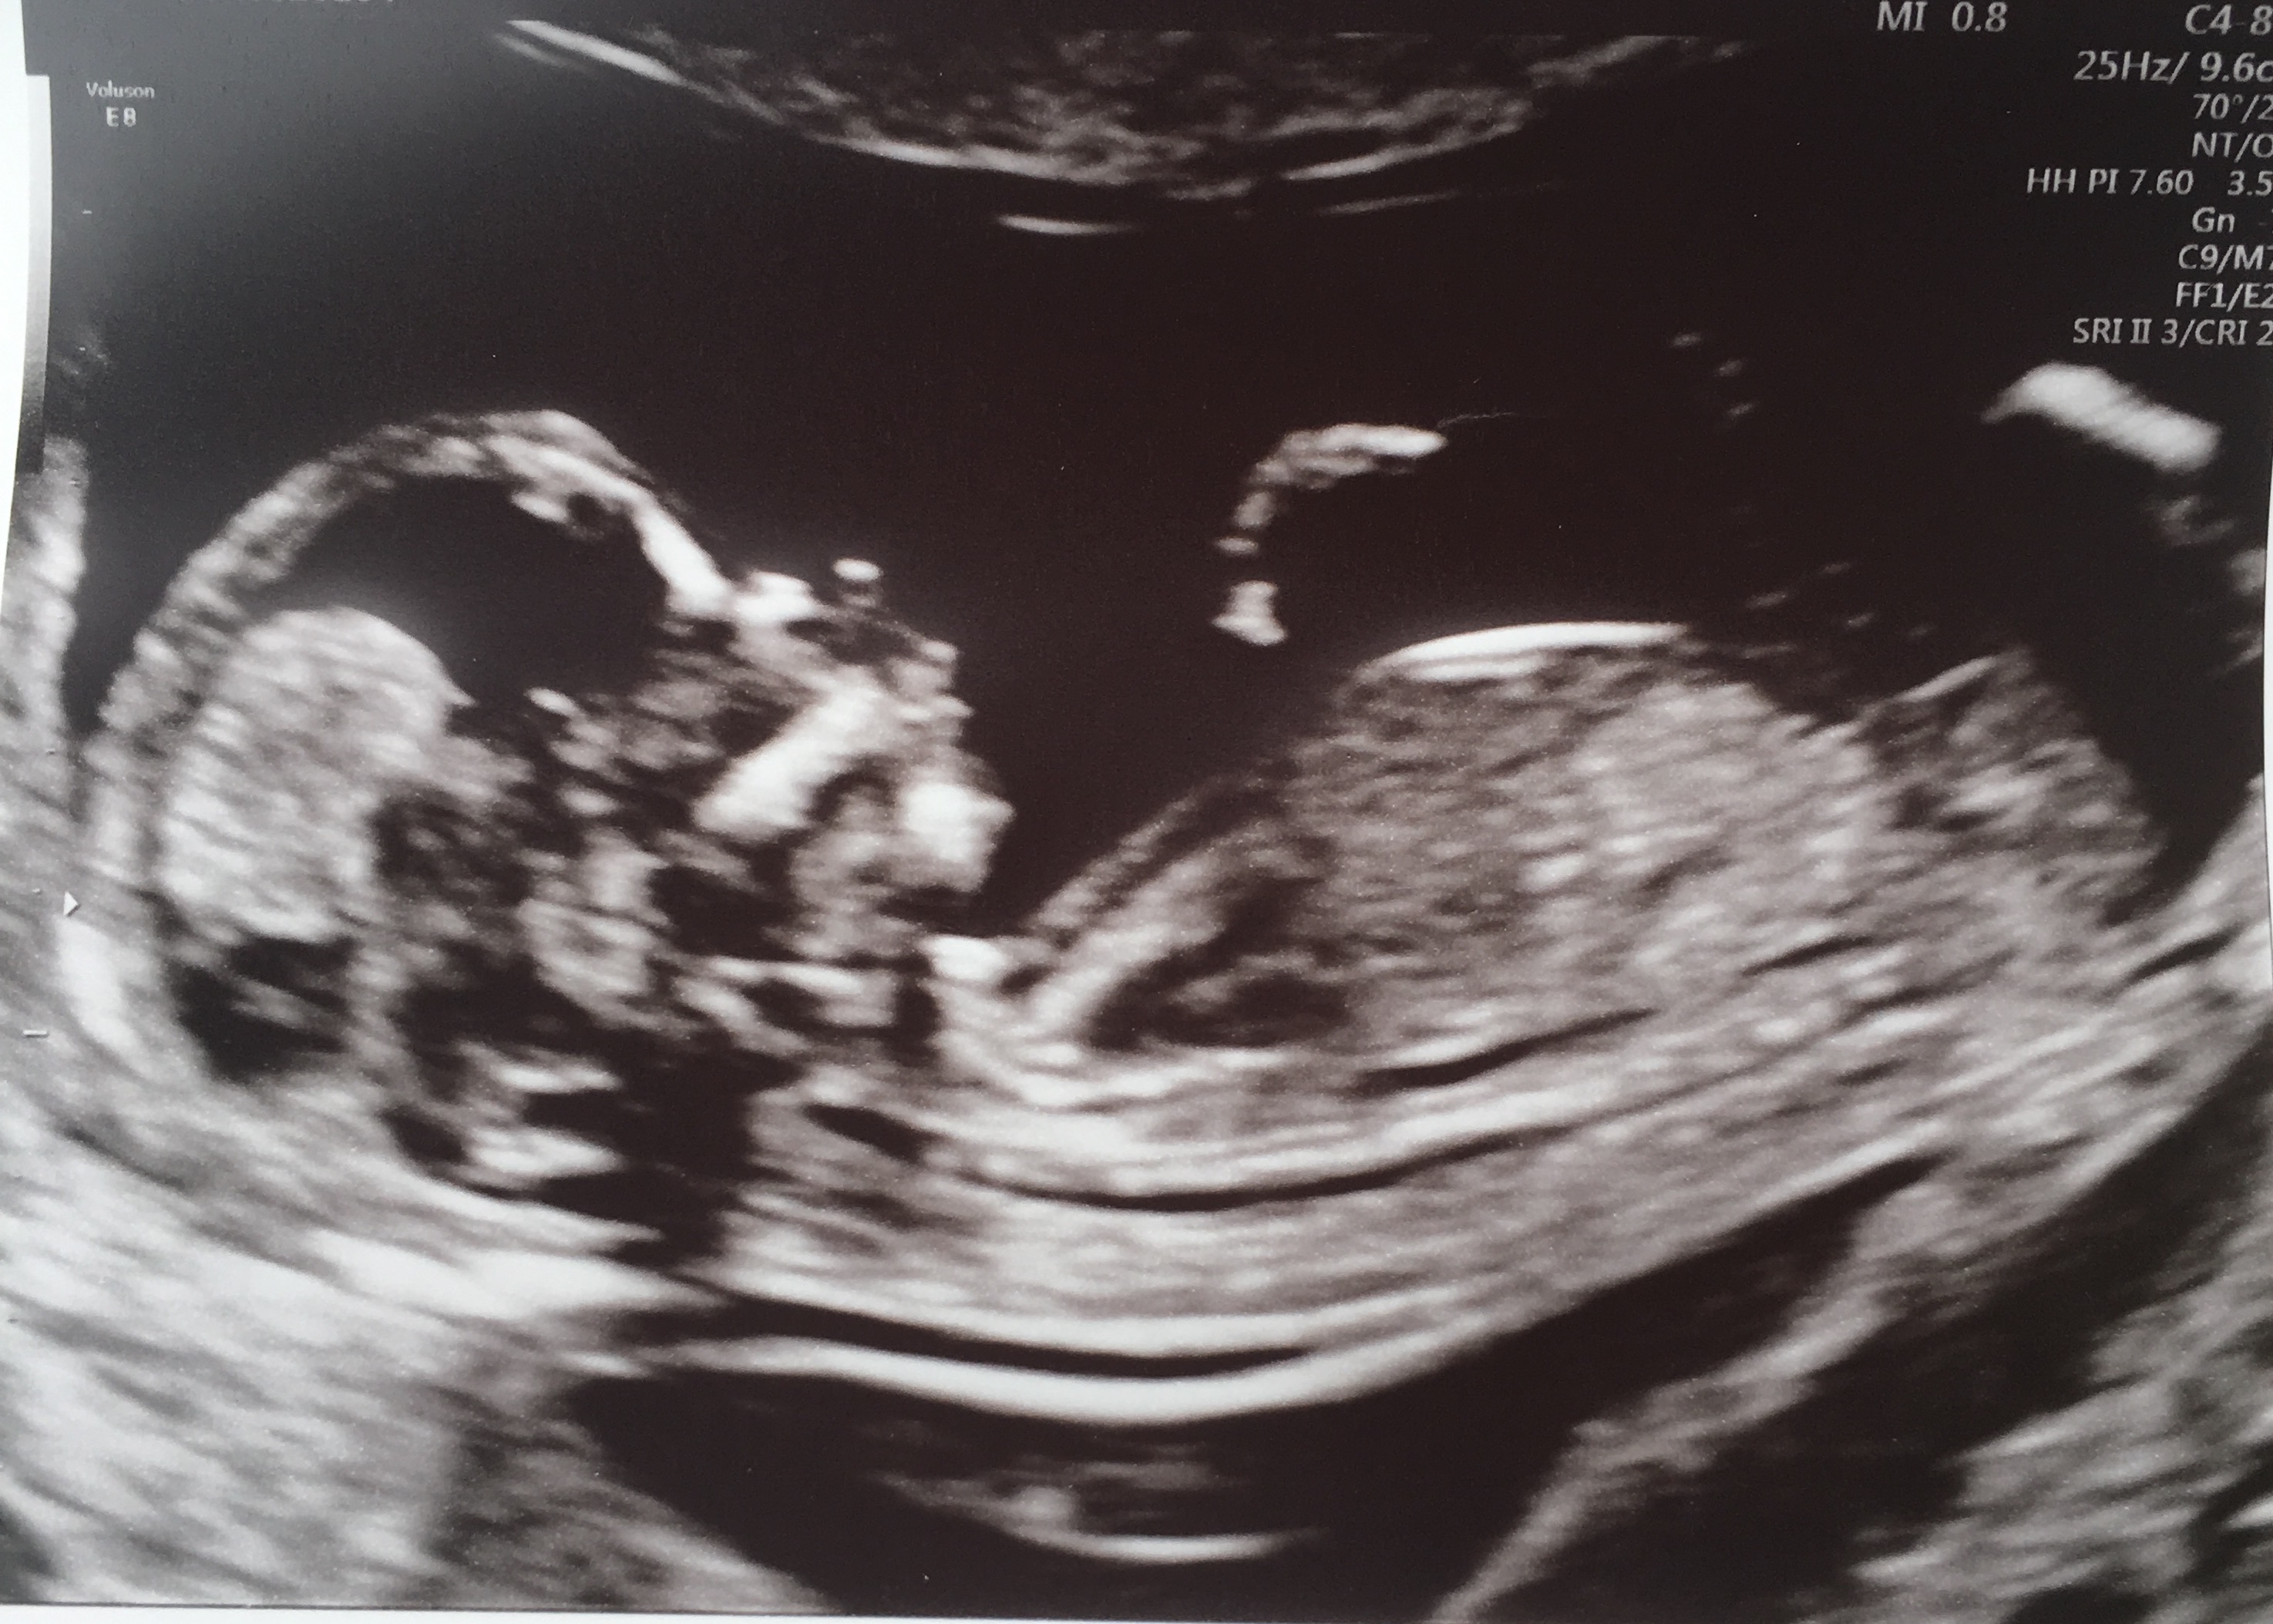

Thank you, I feel the 1st one looks girly but it’s the 2nd image that’s throwing me xx

I would give a girl lean off the first pic but a boy lean off the second... 50/50 and absolutely no help to you at all sorry. Will be interested to know though when you find out so plese update! I am an amateur guesser [emoji4]

Thank you I agree with you. It’s driving me crazy 🙈 I thought 13+4 would be such a good gestation to guess but baby kept turning making it difficult to see nub. Wondering if 2nd pick could possibly be a foot or something. Thanks for guessing because tge 1st seems so straight for the gestation. Thanks for looking xx

Oh thank you so much 😊 you’ve really given me some hope for my girl. I’m usually good at guessing others but so hard when it’s your own. Would you say it looks like cord in the 3rd pic also? xx